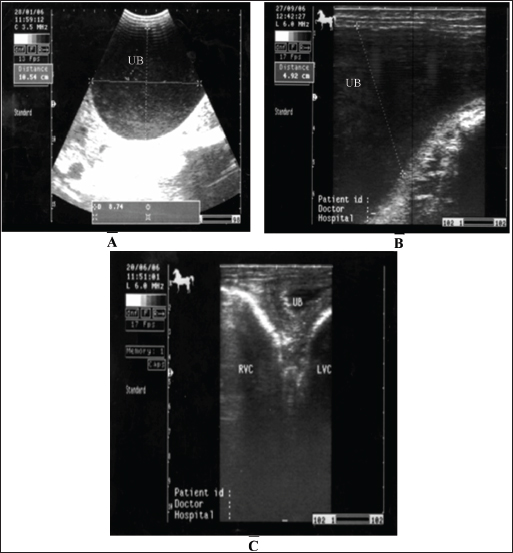

Fig. 18. A sonogram of horses suffering from cystitis showed. Images A and B were obtained from the transrectal window using an 8-MHz linear transducer. Corrugation of the bladder wall (A) and hyperechogenicity of the bladder contents with distal acoustic enhancement (B). Images C and D were obtained from the transrectal window using a 6-MHz transducer. Notice hyperechogenicity of the bladder contents, which leads to acoustic enhancement (C and D). UB=urinary bladder.

Fig. 19. Sonogram of horses with urine retention showed. In images A and B, the urinary bladder appears distended. In image C, the bladder collapses after catheter application. These sonograms were obtained from the transrectal window using a 6-MHz transducer. Image A was taken transcutaneously using a 3.5-MHz sector probe, while images B and C were taken transrectally using a 6.0-MHz linear transducer.

Horses suffering from urine retention also showed severe restlessness with failure in urinate testing. History and clinical manifestations are usually diagnostic. The urinary bladder was imaged, revealing a marked distension with echogenic urine causing distal enhancement and hyperechoic sediment ventrally in the bladder. The bladder wall is normal unless concurrent cystitis is present (Abu-Seida and Shamaa, 2020). After catheter application, the urinary bladder returns to normal size, and the wall will also be normal (Fig. 19). Management of cystic calculi is performed by surgical removal of the calculi and correction of any bladder perforation, if present. Ultrasound-guided, transcutaneous right kidney nephrostomy has been reported in a horse with ureteral calculi for the purpose of short-term diversion of urine (Duesterdieck-Zellmer, 2007). Surgically, sub-ischial urethrotomy may be conducted under epidural anesthesia (Abu-Seida and Shamaa, 2020).

Horses with cystitis show signs of pollakiuria, hematuria, pyuria, stranguria, and urine scalding in the perineum in mares or in front of the hind legs of male equines (Smith, 2015). Usually, females are affected more frequently than males. In cases of cystitis, diffuse or focal thickening and irregularity of the bladder wall are the most common imaged abnormalities detected in horses with diseases, and the urine is usually echogenic to hyperechoic (Le Jeune and Whitcomb, 2014). Staining, arched back, and maiming urination posture for a long time are also observed. Case history and clinical signs are usually diagnostic in most cases. Pronounced thickening of the bladder wall is the most frequently observed finding on ultrasonography of the bladder, and the urine is more echogenic (Zakia et al., 2021). In addition, fibrin strands are imaged in equines with intense cystitis, whereas in healthy animals, the urinary bladder wall appears echogenic and the urine appears anechoic with hyperechoic particles (Fig. 18). Antimicrobials are prescribed to eliminate infections, and the verification of the antimicrobial sensitivity of the causative agent is crucial. Recurrence is common unless therapy is continued for a period of 7–14 days. Repeated urine culture at least once during treatment and within 7–10 days after treatment should be performed to estimate the success or failure of therapy (Reed et al., 2004).